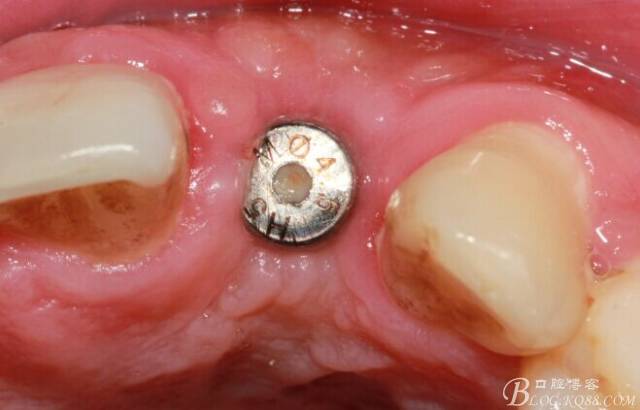

翻開(kāi)后驚喜的發(fā)現(xiàn),術(shù)區(qū)成骨非常好,去除部分骨才暴露那顆長(zhǎng)鈦釘。

取出影響種植入路的長(zhǎng)鈦釘。